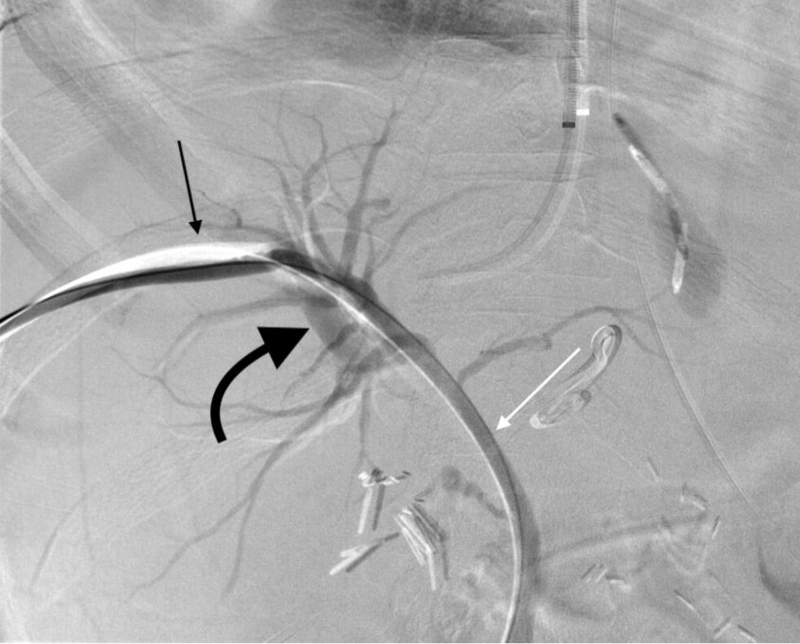

PTBD đường mật (Percutaneous Transhepatic Biliary Drainage – dẫn lưu đường mật qua da) là một phương pháp can thiệp quan trọng trong điều trị tắc nghẽn đường mật. Đây là một kỹ thuật xâm lấn được thực hiện nhằm giải quyết các tình trạng tắc nghẽn đường mật do nhiều nguyên nhân khác nhau, giúp giảm tình trạng ứ mật, cải thiện chức năng gan và phòng ngừa những biến chứng nghiêm trọng. Phương pháp này được thực hiện bằng cách sử dụng kim chọc qua da vào gan và đường mật, sau đó đặt một ống thông để dẫn lưu dịch mật ra ngoài cơ thể hoặc vào ruột non, giúp giải phóng ứ đọng và hỗ trợ quá trình điều trị bệnh.

Quy trình thực hiện PTBD đường mật là một thủ thuật can thiệp quan trọng để điều trị tắc nghẽn đường mật, giúp giảm tình trạng ứ mật và phòng ngừa các biến chứng nghiêm trọng. Phương pháp này đòi hỏi sự thực hiện cẩn thận và chính xác, nhằm đảm bảo an toàn cho bệnh nhân và hiệu quả điều trị. Dưới đây là quy trình khi thực hiện phương pháp PTBD đường mật mà bạn nên biết: